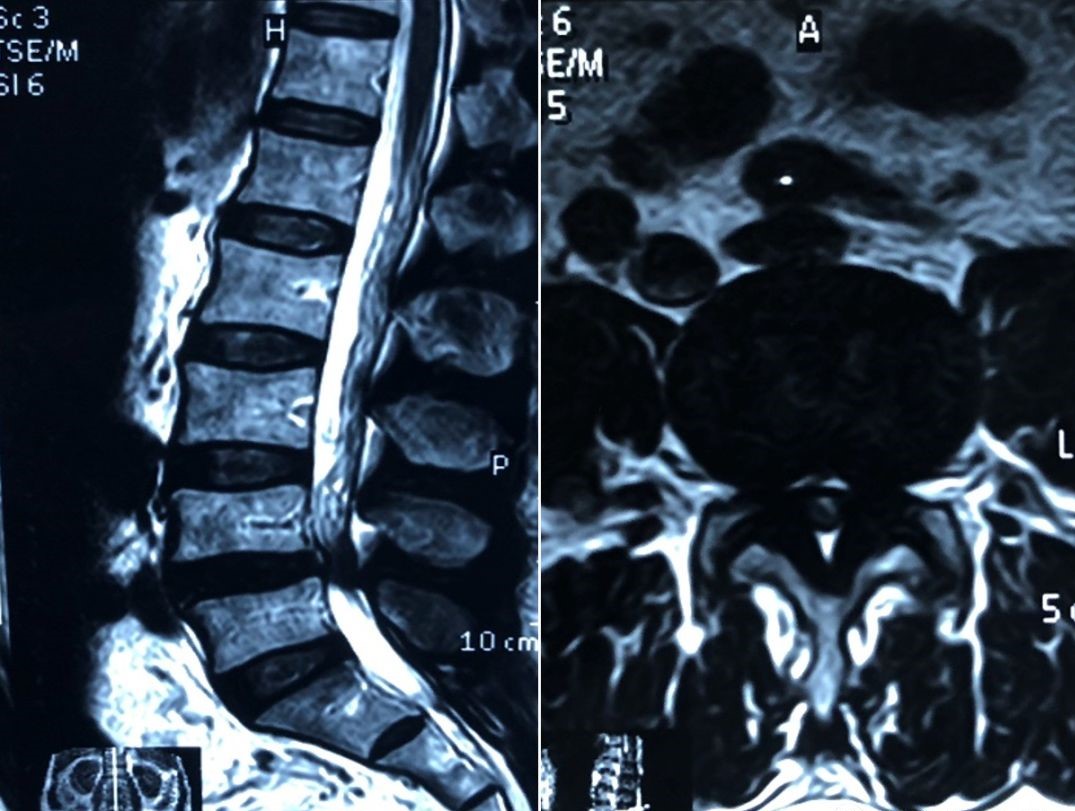

过年后,梁姨就迫不及待地前往医院就诊,外院诊断梁姨是 腰椎椎管狭窄症 ,腰椎磁共振上显示梁姨的椎管严重狭窄,压迫神经,治疗需要手术进去摘除椎间盘,并且需要打上四颗螺钉固定。

磁共振提示梁姨有严重的椎管狭窄